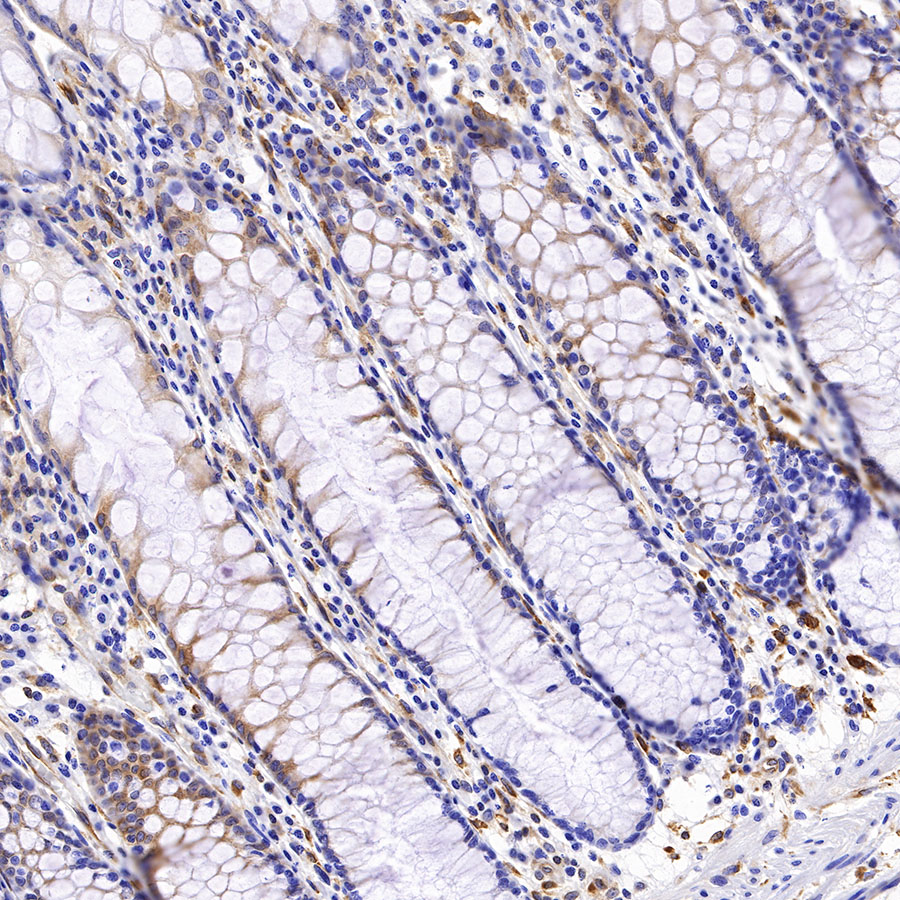

Picture

Picture

Immunohistochemistry